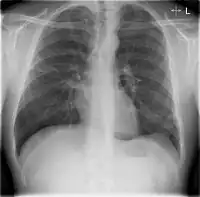

Chest X-rays and X-ray computed tomography (CT) can reveal areas of opacity (seen as white), indicating consolidation.[13] CAP does not always appear on x-rays, sometimes because the disease is in its initial stages or involves a part of the lung not clearly visible on x-ray. In some cases, chest CT can reveal pneumonia not seen on x-rays. However, congestive heart failure or other types of lung damage can mimic CAP on x-ray.[15]

When signs of pneumonia are discovered during evaluation, chest X-rays and examination of the blood and sputum for infectious microorganisms may be done to support a diagnosis of CAP. The diagnostic tools employed will depend on the severity of illness, local practices and concern about complications of the infection. All patients with CAP should have their blood oxygen monitored with pulse oximetry. In some cases, arterial blood gas analysis may be required to determine the amount of oxygen in the blood. A complete blood count (CBC) may reveal extra white blood cells, indicating infection.